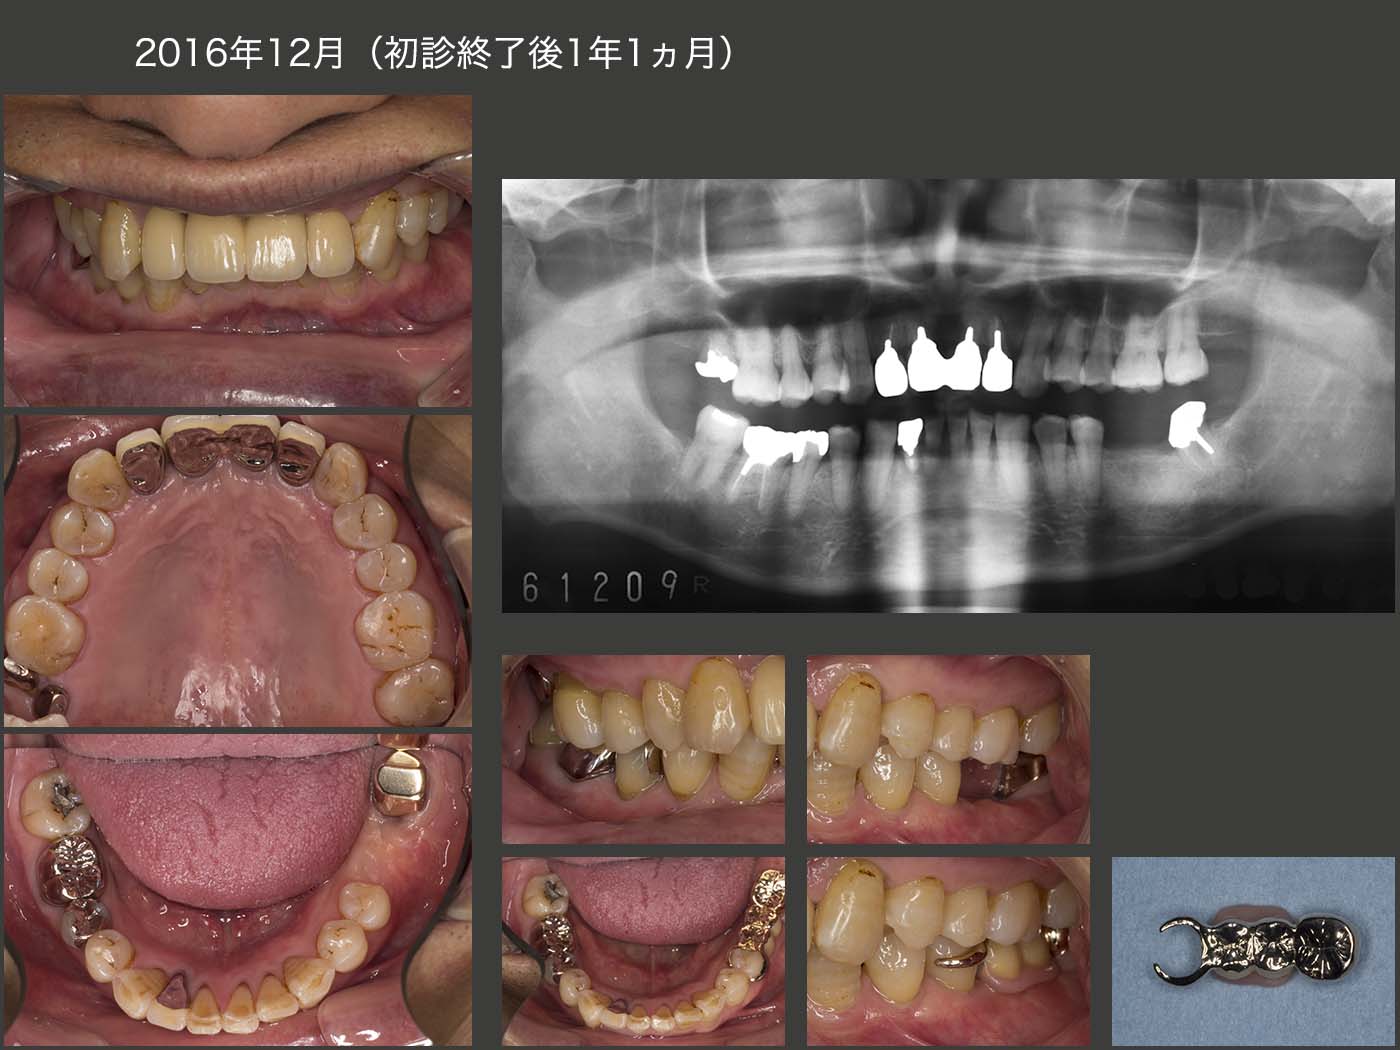

上顎2〜2は,2014年6月に両側中切歯にコアおよび暫間被覆冠装着し,1年5ヵ月間経過を観察した後の15年11月にメタルボンド冠を装着し,ここで初診終了とした.なお,この期間中に他部位の治療(15年8月,左下の可撤式ブリッジ装着)も行っていた.